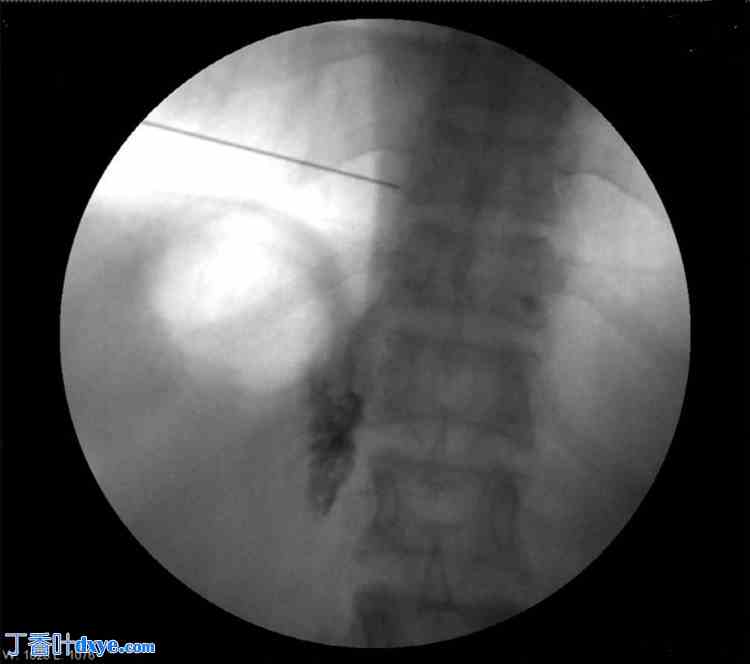

患者取俯卧位。涂抹并铺巾后,在C臂辅助下将T8横突定位于右侧。在透视引导下插入Quincke针(22 G),到达T8横突。针尖沿横突向尾部推进,直至感觉无阻力。在透视下注射碘海醇300放射性造影剂确认针头位置,并拍摄前后位和侧位图像(图1-4)。

图2. 注射碘海醇300放射性造影剂后的前后位透视图。